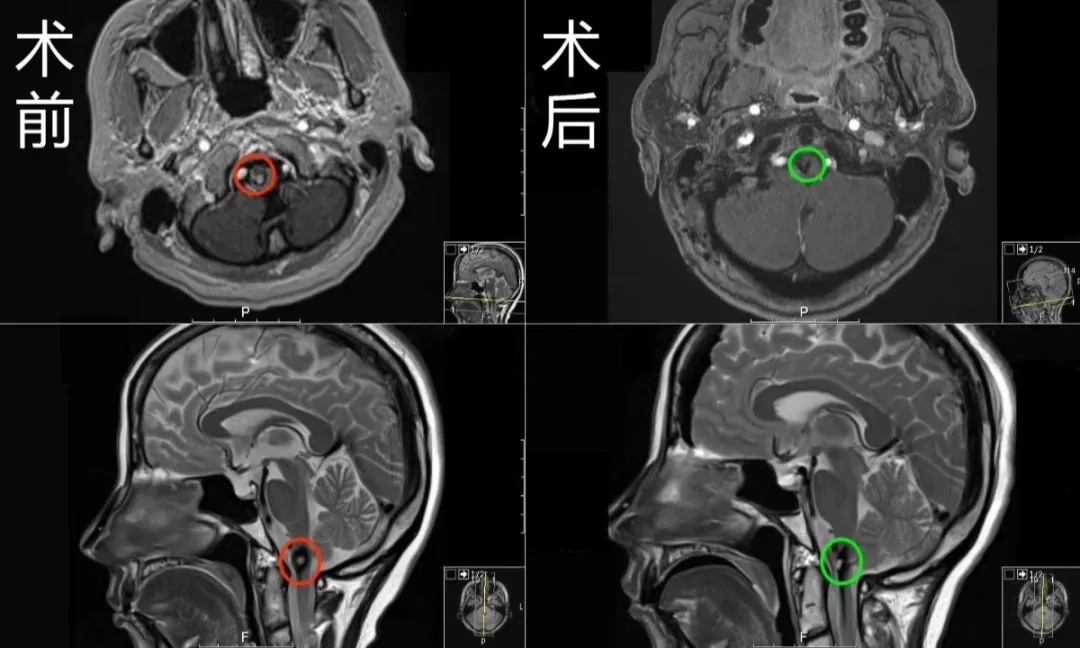

(术前术后MR对比)

术前MR:延颈髓偏右侧见一直径约1cm占位,周围见环状含铁血黄素低信号影环绕,提示海绵状血管瘤。